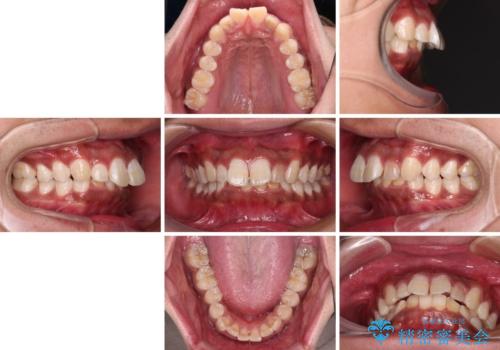

- 深く咬みこみ、前に飛び出した上顎前歯を気にして来院された患者様です。

口元の突出感はあまりありませんでしたが、上顎歯列が全体的に前方にあり、更には下顎歯列が深く咬みこんでいるために、上顎前歯が前方に突出している状態でした。

抜歯は行わず、補助装置を用いて上顎歯列全体を後方移動させ、ワイヤー装置にて奥歯の咬み合わせを改善していくこととしました。

正面や横から見た印象が同じで用であっても、奥歯の咬み合わせが理想的であるかどうかによって、治療の難易度は大きく異なります。

こちらの方も難易度のやや高い状態で、2年以上の期間が予想されましたが、想定通りの2年強で治療を終えることができました。